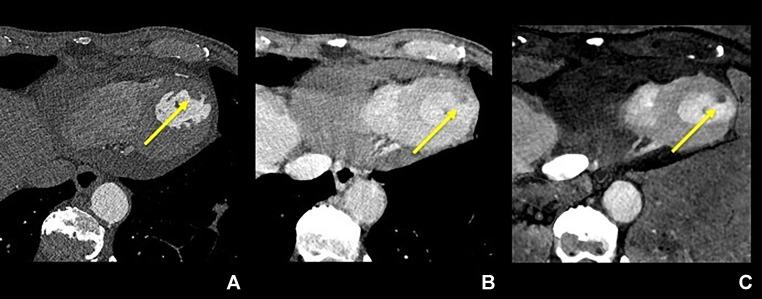

Identification of a small thrombus in the left ventricle identified on iodine maps derived from dual-source photon-counting detector CT.

Transthoracic echocardiography is the main imaging modality to diagnose left ventricular thrombus (LVT), but its efficacy in certain cases is suboptimal. We report a patient in whom an LVT, initially unidentified by transthoracic echocardiography, was successfully diagnosed with iodine maps derived from dual-source photon-counting detector CT (DS-PCD-CT). The 64-year-old male was admitted to our institution following myocardial infarction. Although TTE failed to detect this small LVT, iodine maps derived from CT angiography (which was conducted to evaluate the coronary artery stenosis) revealed its presence. Iodine maps derived from DS-PCD-CT collecting data with high temporal resolution are beneficial to diagnose LVTs.

经胸超声心动图是诊断左心室血栓(LVT)的主要成像方式,但在某些情况下其效果并不理想。我们报告了一名患者,其LVT最初经胸超声心动图未识别出,而通过双源光子计数探测器CT(DS-PCD-CT)获得的碘图成功诊断。该64岁男性在心肌梗死后入住我院。尽管经胸超声心动图未能检测到这个小LVT,但为评估冠状动脉狭窄而进行的CT血管造影所获得的碘图显示了其存在。由具有高时间分辨率的数据采集的DS-PCD-CT获得的碘图有助于诊断LVT。